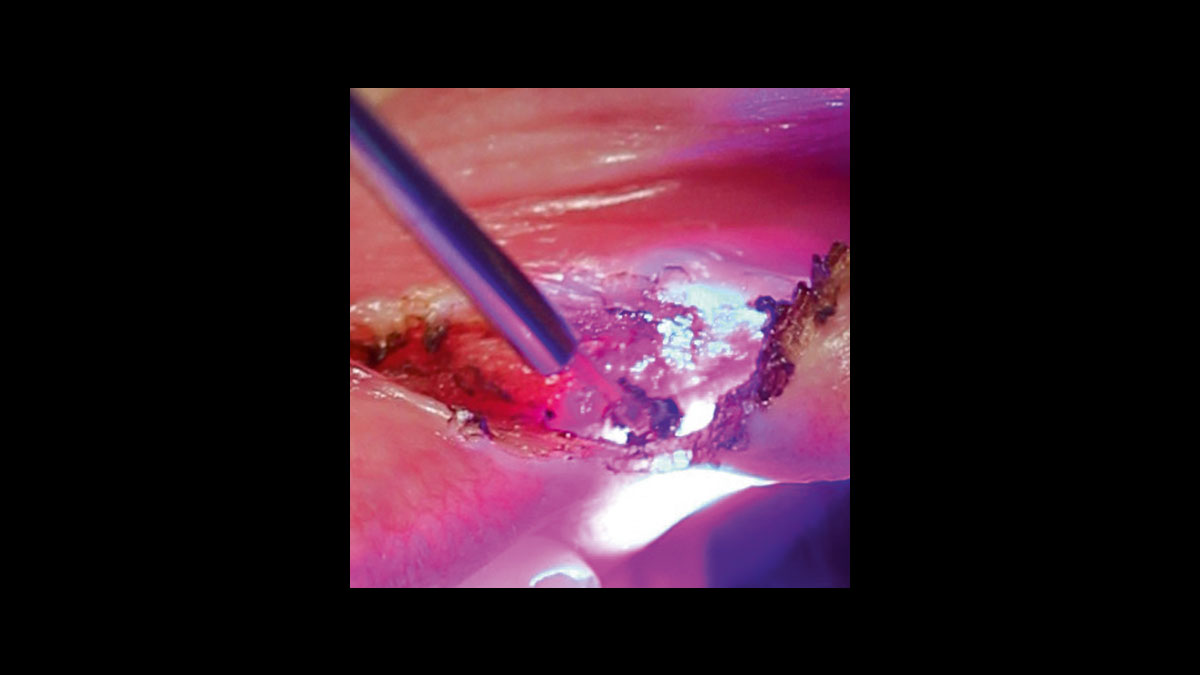

• Gingival troughing

Gingival troughing